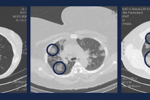

Koronawirus jest już w Polsce. Co można robić i jak się zabezpieczać przed wirusem Sars-CoV-2? Kiedy i komu jest potrzebna maseczka na twarz?

Rzadko słyszymy o tym, że zarażeniu się wirusem Sars-CoV-2 uległo dziecko. Z jednej strony eksperci zastanawiają się, dlaczego tak się dzieje, z drugiej cieszą się, ponieważ jest szansa na szybsze wygaszenie epidemii.

Aby ustrzec się przed groźnym dla życia i zdrowia koronawirusem należy często myć ręce. Gdy jednak nie mamy takiej możliwości z pomocą przychodzą żele antybakteryjne. Tych jednak zaczęło brakować na sklepowych półkach. Dlatego przedstawiamy prosty przepis na domowej roboty żel antybakteryjny na koronawirusa.